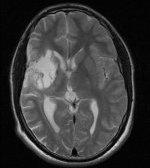

T2-gewichtetes MRT |

Organisches Gewebe enthält viel Wasser und Fett. Diese Stoffe

bestehen im Mensch aus ca. 63% Protonen. Setzt man Protonen einem

magnetischen Feld aus, schwingen sie entsprechend der Feldstärke.

Diese absorbierte Energie geben sie wieder ab, was man messen kann.

Die Signalstärke wird durch jedes Proton leicht variiert.

Läßt

man ein zusätzliches Magnetfeld einwirken, das in Stärke und Lage

variiert wird, läßt sich durch die unterschiedliche Resonanz der

Felder pro Ort eine elektromagnetische Strahlung messen. Daraus kann

man ein 3D-Bild berechnen.

Schädel

seitlich

T2-gewichtetes

MRT |